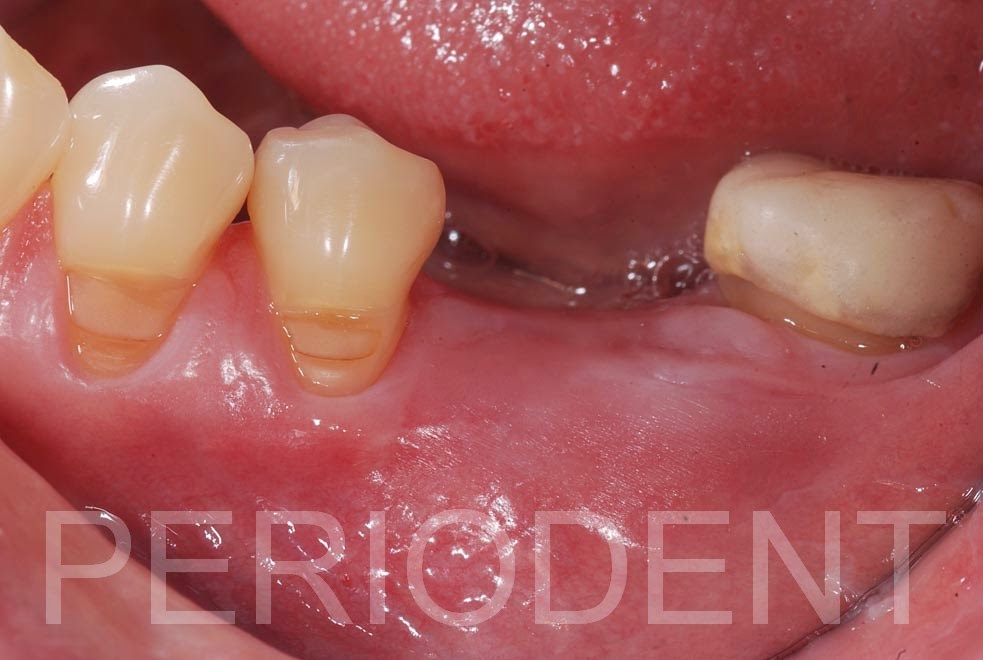

患者的左下第一大臼齒有牙根縱裂需拔除

經過六個月後,利用Cytoplast及骨粉進行補骨

癒合後